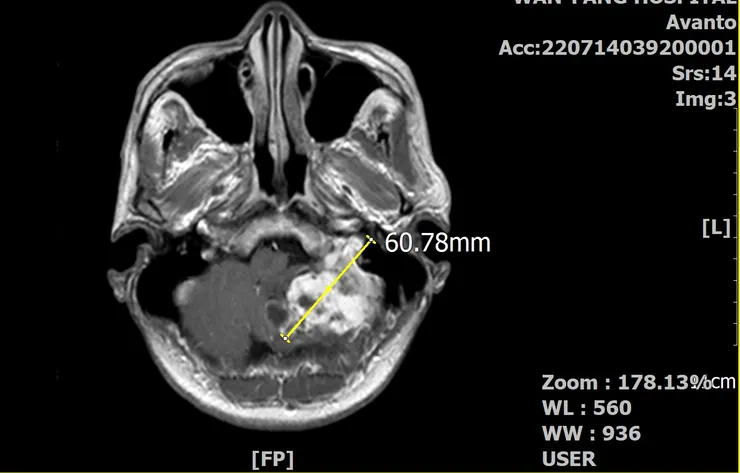

椰當年在MRI下的龐大身軀(水平剖面)

當時的椰已經6公分了,這體積早把我的腦幹都「擠歪」了。影響最的的是聽力跟平衡的狀況,於是我逐漸失去了左耳的聽力,以及走在亂石堆的郊山步道上,總是很怕跌倒(不是體力差)。